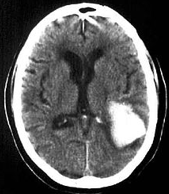

Intraparenchymal hemorrhage

uSevere contusion, laceration or penetrating injury

uFocal

uMay present as coup-contre coup

uSuborbital, anterior temporal lobe

uBlood pools in white matter of brain.

uBrain trauma can cause several severe IPHs, and can result in white matter shear injury—extensive loss of axons w/extensive brain injury.

uThis can cause diffuse axonal injury.